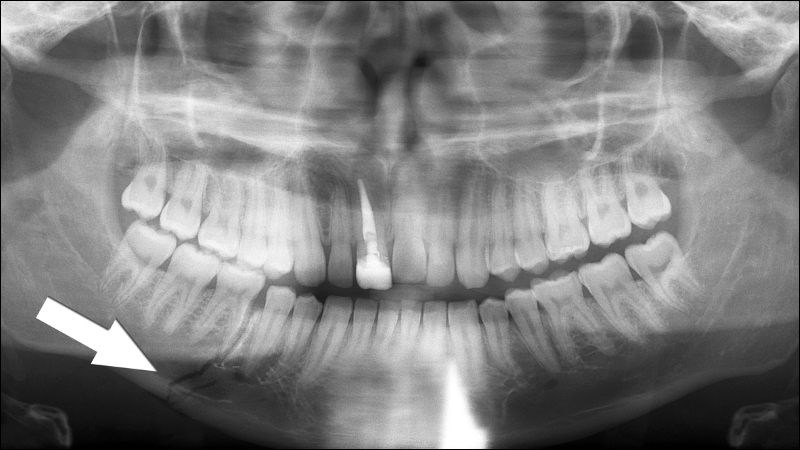

Sau khi đã khám lâm sàng và nghi ngờ gãy xương hàm, bác sĩ sẽ chỉ định chụp phim X-quang vùng xương hàm để chẩn đoán xác định.

Ngoài ra, trong một số trường hợp hình ảnh gãy xương trên phim X-quang không được rõ ràng, bác sĩ có thể yêu cầu chụp thêm hình ảnh CT (chụp cắt lớp vi tính) để xác định rõ mức độ và vị trí chỗ gãy.

X-quang là phương tiện chẩn đoán gãy xương hàm hiệu quả, nhanh chóng